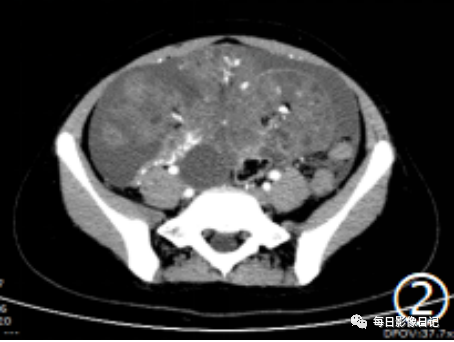

【影像所见】:

平扫腹部囊实性混杂密度肿块,以实性为主呈片絮状,可见散在不规则钙化(红箭示)及脂肪密度(白箭示),可见多个小囊,囊壁厚薄不一;

动脉期肿块实性部分及囊壁呈轻度不均匀强化;

静脉期及延迟期实性部分及囊壁进一步强化,可见包膜(蓝箭示指);

可见其内增粗穿行肿瘤血管(红箭示)及小囊(粗白箭示),另见腹腔大量积液。